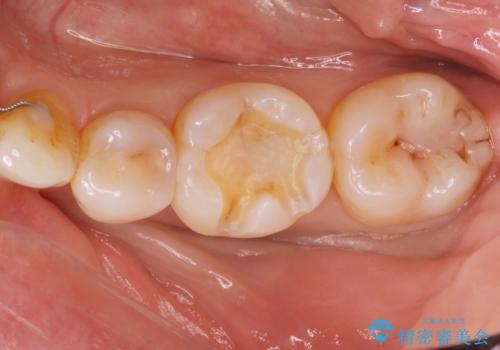

- 過去に治療した銀の詰め物が取れて来院された患者様です。

詰め物のやりかえをするのなら白い詰め物でやりかえたいとのことなのでe-maxインレーでの治療を行いました。